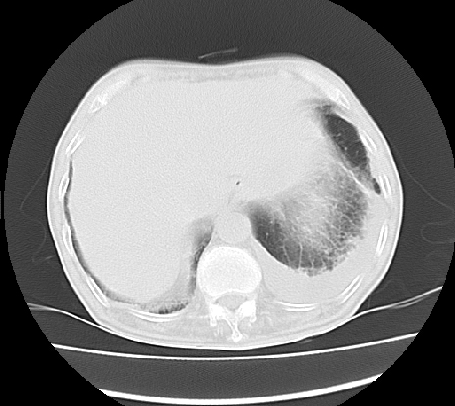

门脉期